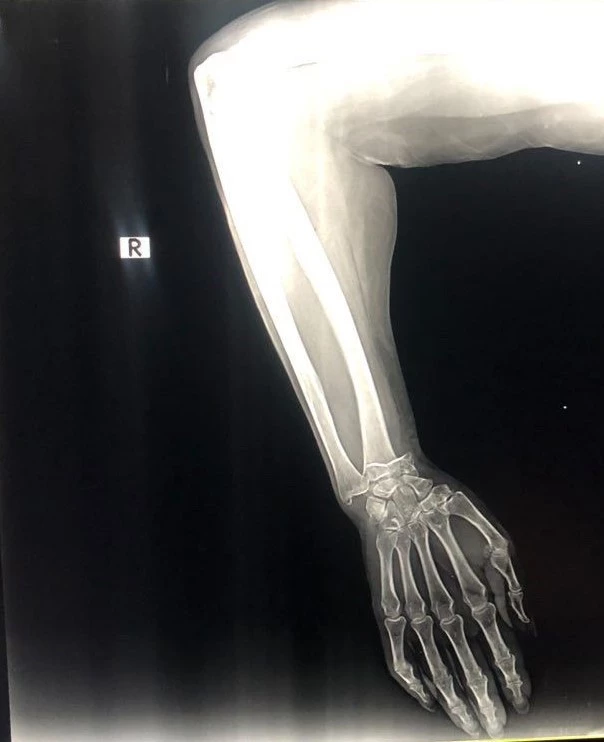

Antalya’da kızıyla pazar alışverişi yaparken bileği kırılan Ukraynalı kadına, giriş yaptığı özel hastanede bin 650 dolar fatura çıkarıldı. Duruma tepki gösteren ailenin itirazı üzerine hastane yönetimi 850 doları iade etti. Kalan 800 doları da fazla gören ailenin Türk damadı, 'Yatış yok, bıçak yok, ameliyat yok ve bin 650 dolar fiyat çıkıyor. 850 doları geri yatırdılar ama bu alçıya 800 dolar da fazla' diyerek tepki gösterdi. Olay, 4 Ağustos Cuma günü Kemer ilçesi Aslan Bucak Mahallesi Cuma pazarında yaşandı. Savaştan kaçıp Antalya’ya yerleşen Olena Buletsa (61), burada Şeyhmus Doğan ile yakın bir tarihte evlenen kızı Kateryna Buletsa’la (32) pazar alışverişine çıktı. Kızıyla birlikte yürüdüğü sırada dengesini kaybedip yere düşen Olena Buletsa’nın bileği kırıldı. Çevredekilerin durumu 112 Acil Çağrı Merkezine bildirmesi üzerine Buletsa ambulansla Özel Kemer Yaşam Hastanesine götürüldü. Burada iddiaya göre, sadece röntgen ve alçıya bin 680 dolar (günün kuruyla 44 bin 555 TL) fatura kesildi. Buletsa ve kızı bu parayı ödeyip evlerine döndü. Faturayı gören damadı Şeyhmus Doğan hastaneye gidip faturaya hastane çalışanları ve yetkililerine tepki gösterip itiraz etti. Olaydan bir gün sonrası ise 850 dolar geri yatırıldı. Hala olayın şokunda olan aile, paranın bir bölümünün geri yatırılmasına rağmen 800 doları fazla bulduklarını savundu. 'RÖNTGEN ÇEKİLDİ, CERRAH KOLU DÜZELTTİ VE BİR ALÇI UYGULADI' Bileği kırılan kadının kızı Kateryna Buletsa, olayı şu sözlerle anlattı: 'Cuma günü annemle çarşıya gittik. Sebzelerin yanında çok su vardı. Annem kaydı ve düştü. İnsanlar yardım etti, ambulans çağırdı. Ambulans geldiğinde sigorta olup olmadığını sordular. Ne yazık ki yoktu. Ukrayna’da bir savaş var. Şimdi yaşamak zor. Hangi hastaneye götürüldüğümüzü bilmiyordum. Orada doktorlar tıbbi bakım sağlamaya başladı. Ücretsiz olmadığını söylediler. Başka bir kliniğe gidelim dedim. Doktor ’Türkiye’nin her yerinde pahalı’ dedi. Röntgen çekildi. Cerrah kolu düzeltti ve bir alçı uyguladı. Bin 650 dolarlık bir fatura çıkardılar. Sonra acilen ameliyat gerektiğini söylediler.' '850 DOLARINI GERİ YATIRDILAR' Şeyhmus Doğan, “Hastaneye geldiklerinde sadece bir röntgen ve bu alçıyı yapıyorlar. Yatış yok, bıçak yok, ameliyat yok ve bin 650 dolar fiyat çıkıyor. Eşim devlet hastanesine gitmek istiyor, orası daha fazla para alır diyerek onu bu parayı ödemeye zorluyorlar. 44 bin 500 TL ödediler, 10 adet sargı bezi ve transfer. Ertesi gün ben gittim ve itiraz ettim. Polis çağırmamamı istediler. 850 dolarını geri yatırdılar. Kalan 800 dolar. Yine de bu alçıya 800 dolar verilir mi? Bu insanlar savaştan kaçtı, ben asgari ücretle çalışan birisiyim. Büyüklerimizin sesimizi duymasını istiyorum” diye konuştu. /HABERLER.COM